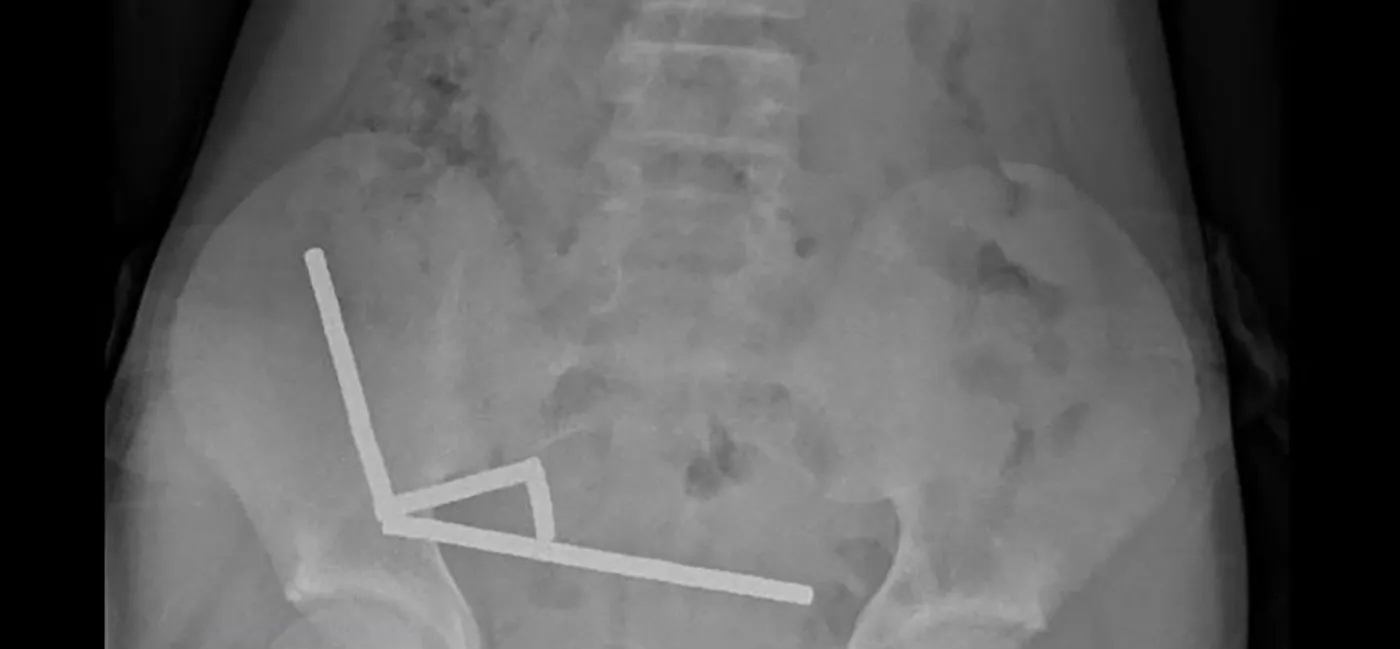

وبحسب تقرير طبي نُشر في المجلة الطبية النيوزيلندية، فإن المغناطيسات تكتلت داخل أمعاء الطفل في أربعة خطوط مستقيمة، وسبّبت التصاق أجزاء من الأمعاء ببعضها بفعل القوى المغناطيسية، ما أدى إلى موت أنسجة في الأمعاء الدقيقة والغليظة، واضطر الجراحون إلى إزالة الأنسجة المتضررة والقطع المغناطيسية.